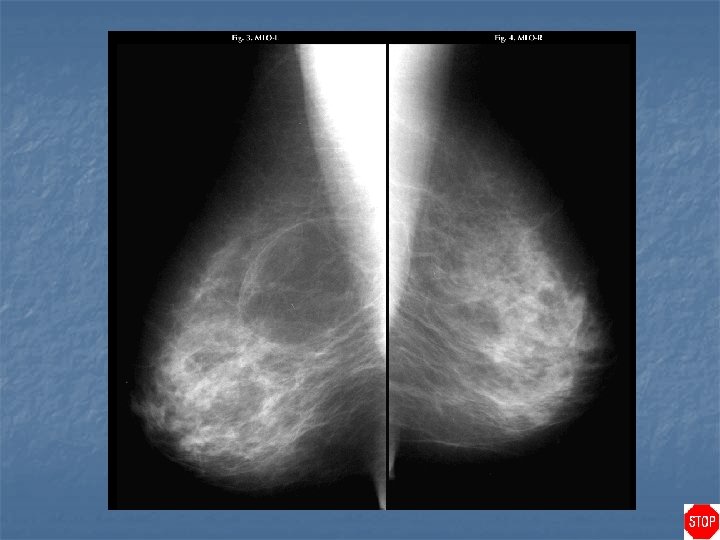

Rheumatoid arthritis n Case findings: n n Enlarged dense axillary lymph nodes DDX of enlarged axillary lymph nodes: n n n BCA with lymph node metastasis Lymphoma HIV RA TB, sarcoidosis Benign reactive nodal hyperplasia

Metallic deposits in axillary nodes from RA gold injections

Case directory Rheumatoid arthritis n DDX of calcified axillary lymph nodes: MC metastasis (ovarian, mucinous tumors) n RA with gold treatment n Treated lymphoma n